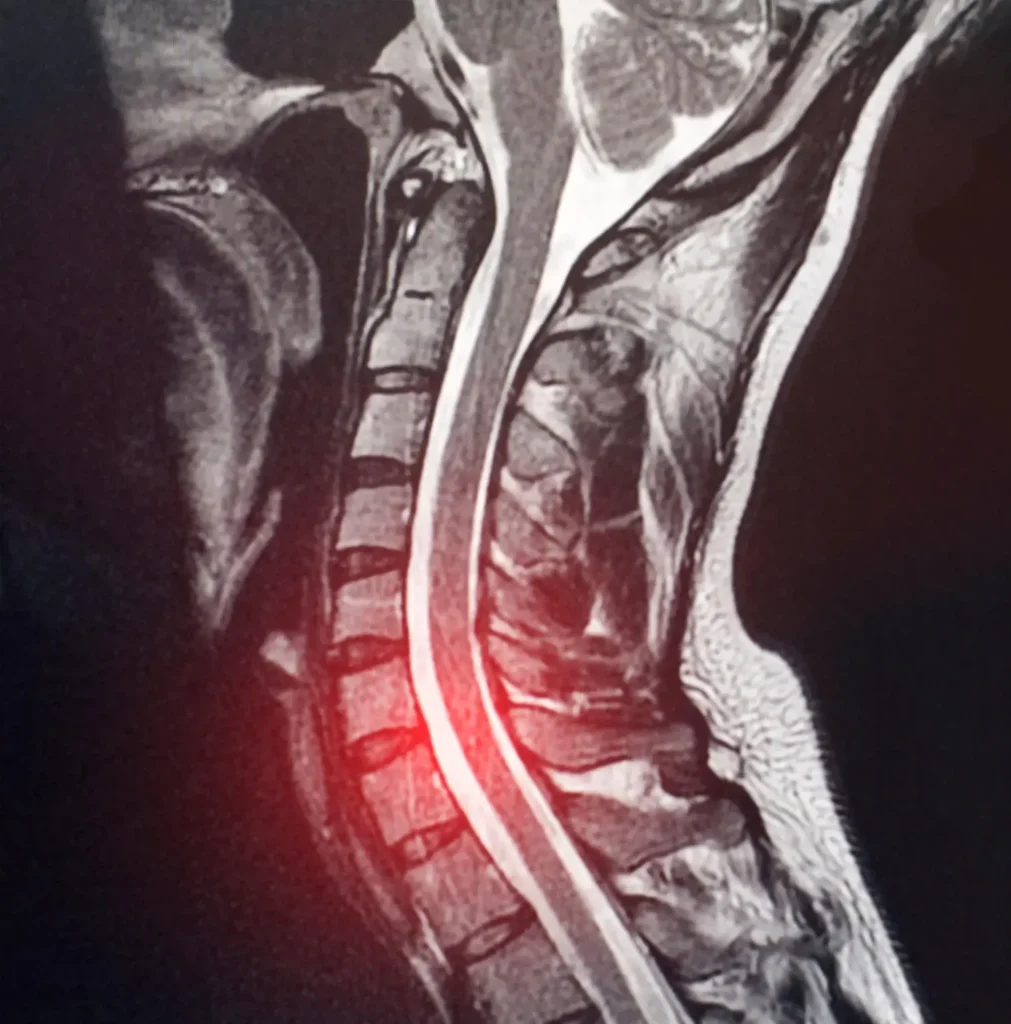

- Thoái hóa cột sống nghiêm trọng: Nếu cột sống cổ đã bị thoái hóa khớp diện khớp hoặc đĩa đệm đã xẹp trên 50%, phẫu thuật thay đĩa đệm cổ ít có khả năng giúp giảm đau và duy trì vận động tại phân đoạn đó. Các triệu chứng kéo dài càng lâu, khả năng tổn thương thần kinh vĩnh viễn đã xảy ra càng cao và không thể phục hồi bằng phẫu thuật.